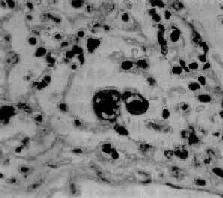

图9-19 支气管肺炎 图中见灶状实变的肺组织,肺泡内充满以中性粒细胞为主的炎性渗出物;病灶中有发炎的细支气管 【并发症】 小叶性肺炎发生并发症的危险性比大叶性肺炎大得多。可并发心力衰竭、呼吸衰竭、脓毒败血症、肺脓肿及脓胸等。支气管破坏较重且病程较长者,可导致支气管扩张。 【临床病理联系】 因小叶性肺炎多为其他疾病的并发症,其临床症状常为原发性疾病所掩盖。由于支气管粘膜的炎症刺激而引起咳嗽,痰呈粘液脓性。因病变常呈灶性散布,肺实变体征一般不明显。病变区细支管和肺泡内含有渗出物,听诊可闻湿啰音。X线检查,可见肺野内散在不规则小片状或斑点状模糊阴影。本病发现及时,治疗得当,肺内渗出物可完全吸收而痊愈。但在幼儿,年老体弱者,特别是并发于其他严重疾病时,预后大多不良。 (二)病毒性肺炎 病毒性肺炎(viral pneumonia)常常是因上呼吸道病毒感染向下蔓延所致。患者多为儿童,症状轻、重不等,但婴幼儿和老年患者病情较重。一般多为散发,偶可酿成流行。引起肺炎的病毒种类较多,常见的是流感病毒、还有呼吸道合胞病毒、腺病毒、副流感病毒、麻疹病毒、巨细胞病毒等等,也可由一种以上病毒混合感染并可继发细菌感染。病毒性肺炎的病情、病变类型及其严重程度常有很大差别。 【病理变化】 早期或轻型病毒性肺炎表现为间质性肺炎,炎症从支气管、细支气管开始,沿肺间质发展,支气管、细支气管壁及其周围、小叶间隔以及肺泡壁等肺间质充血、水肿,有一些淋巴细胞和单核细胞浸润,肺泡壁明显增宽(图9-20)。肺泡腔内一般无渗出物或仅有少量浆液。病变较重者,肺泡也可受累,出现由浆液、少量纤维蛋白、红细胞及巨噬细胞组成的炎性渗出物,甚至可发生组织坏死。有些病毒性肺炎(如流感病毒肺炎,麻疹病毒肺炎、腺病毒肺炎等)肺泡腔内渗出较明显,渗出物浓缩凝结成一层红染的膜样物贴附于肺泡内表面,即透明膜形成。支气管上皮的肺泡上皮也可增生,甚至形成多核巨细胞。麻疹病毒肺炎的病变特点为在间质性肺炎的基础上,肺泡壁上有透明膜形成,并有较多的多核巨细胞(巨细胞肺炎),在增生的上皮细胞和多核巨细胞的胞浆内和胞核内可检见病毒包含体。病毒包含体常呈球形,约红细胞大小,呈嗜酸性染色,均质或细颗粒状,其周围常有一清晰的透明晕。其他一些病毒性肺炎也可在增生的支气管上皮、支气管粘液腺上皮或肺泡上皮细胞内检见病毒包含体。如腺病毒肺炎可在增生的上皮细胞核内(图9-21),呼吸道合胞病毒肺炎可在增生的上皮细胞胞浆内,巨细胞病毒肺炎也可在增生的上皮细胞核内检见病毒包含体。检见包含体是病理组织学诊断病毒性肺炎的重要依据。

图9-21 腺病毒肺炎 图中央可见肿大肺泡上皮细胞中的核内包含体 有些混合感染,如麻疹病毒合并腺病毒感染,特别是又继发细菌感染的病毒性肺炎,病变更为严重,肺炎病灶可呈小叶性、节段性或大叶性分布。支气管和肺组织明显坏死、出血,并可混杂化脓性病变,从而掩盖了病毒性肺炎原来的病变特征。 (三)支原体肺炎 支原体肺炎(mycoplasmal pneumonia)是由肺炎支原体(mycoplasma pneumoniae)引起的一种间质性肺炎。支原体系介于细菌和病毒之间的微生物,共有30余种,其中多种可寄生于人体,但不致病,仅有肺炎支原体能引起呼吸道疾病。各种肺炎中约有5%~10%乃由肺炎支原体引起。主要经飞沫感染,秋、冬季节发病较多,儿童和青年发病率较高,通常为散发性,偶尔流行。患者起病较急,多有发热、头痛、咽痛及剧烈咳嗽(常为干性呛咳)等症状。胸部检查,可闻干、湿啰音。X线检查,肺部呈段性分布的纹理增加及网织状阴影。白细胞计数有轻度升高,淋巴细胞和单核细胞增多,痰、鼻分泌物及咽喉拭子能培养出肺炎支原体。 【病理变化】 肺炎支原体感染可引起整个呼吸道的炎症。肺部病变常仅累及一个肺叶,以下叶多见。病变主要发生于肺间质,病灶呈段性分布,暗红色,切面可有少量红色泡沫状液体溢出。气管或支气管腔内也可见粘液性渗出物。胸膜光滑。镜下,病变区域肺泡间隔明显增宽,有大量淋巴细胞、浆细胞和单核细胞浸润,肺泡腔内无渗出物或仅有少量混有单核细胞的浆液性渗出液。小支气管和细支气管壁及其周围组织也常有炎性细胞浸润。重症病例,上皮亦可坏死脱落,往往伴有中性粒细胞浸润。支原体肺炎预后良好。死亡率在0.1%~1%之间。